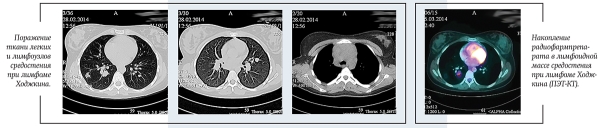

ПЭТ-КТ: в переднем средостении верхнего этажа срединно с акцентом вправо опухолевая масса; 36ґ73ґ60 мм. Изолированно лежащие увеличенные лимфоузлы: паратрахеальные и бифуркационные, до 15 мм; парастернально справа, до 18 мм. По данным ПЭТ: накопление РФП помимо вышеописанных узлов — в правом корне (бронхопульмональные л/узлы), в л/узлах — прекардиально справа, в кардиодиафрагмальной области слева, параэзофагеально (на КТ узел, 14 мм).

Очагов патологической плотности в легочной паренхиме не выявлено. Легочной рисунок не изменен. Долевые и сегментарные бронхи проходимы. Корни легких не расширены, структурны. Подмышечные л/узлы не увеличены. Плевральные полости свободны. Мягкие и костные ткани грудной клетки без структурных изменений. Отмечается увеличение забрюшинных л/узлов, до 23 мм; общих подвздошных до 15 мм. На ПЭТ патологическое накопление РФП помимо вышеописанных узлов — в воротах печени, в наружных подвздошных л/узлах, в селезенке.

Патологических объемных образований в брюшной полости и забрюшинном пространстве не выявлено. Печень не увеличена, однородной структуры. Поджелудочная железа гомогенна, обычных размеров и положения. Почки без видимых изменений.

В левой подвздошной кости определяется очаг гиперденсивной плотности с мелкобугристыми контурами, размером 10,5ґ6,6 мм. На ПЭТ также отмечается повышенное накопление РФП в телах позвонков С6, Тн4, L5, S1; ребрах; костях таза.

Заключение: лимфопролиферативное заболевание с поражением лимфоузлов по обе стороны диафрагмы, селезенки, костей.

Получен полный метаболический ответ по данным ПЭТ-КТ после этапа ПХТ. С целью консолидации ремиссии проведена лучевая терапия на зоны инициального поражения в СОД=20 Гр.